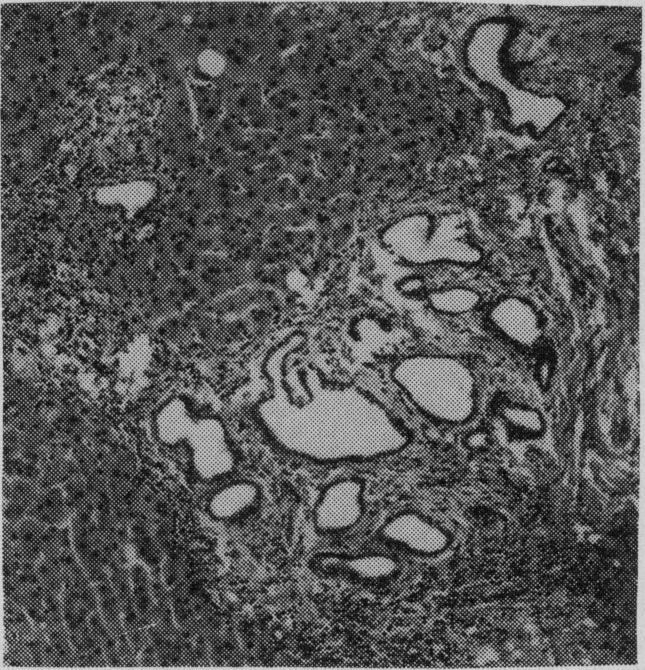

Peutz-Jeghers syndrome with jejunal and colonic adenocarcinomas.

Can Med Assoc J. 1970 Aug 1;103(3):285-7.